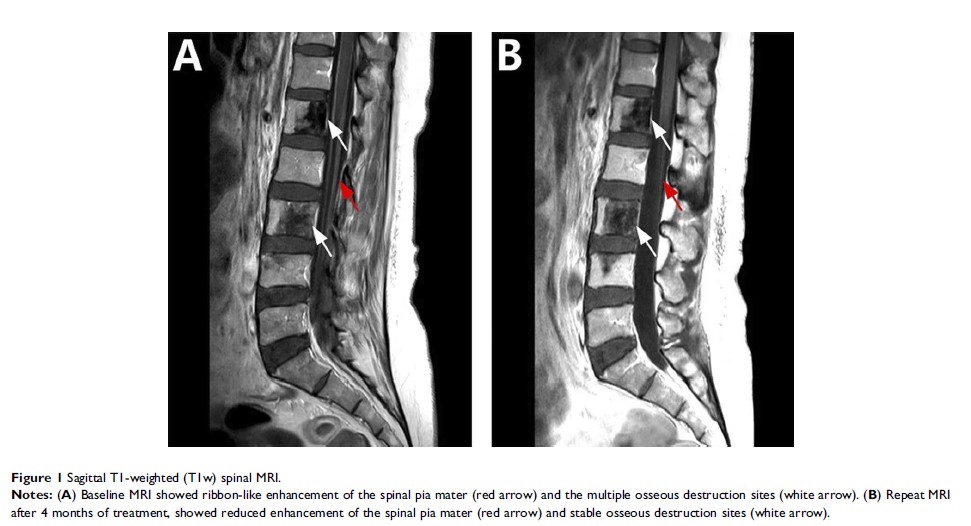

非小细胞肺癌 EGFR 突变的小脑膜转移对奥西替尼治疗的反应:病例系列